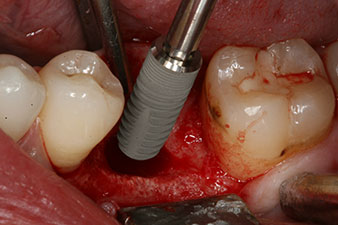

Fig. 3: After preparation with the Implantmed implantology motor, an implant (diameter 4 mm, length 12 mm) was screwed in by the motor at a torque of 43 Ncm.

The implant was placed as planned after thorough removal of the granulation tissue (blueSky, bredent).

The torque used for the machine-driven placement was 43 Ncm. In addition, after screwing a measuring post (SmartPeg) specially matched to the implant, the ISQ value was measured with the probe of the W&H Osstell ISQ module.